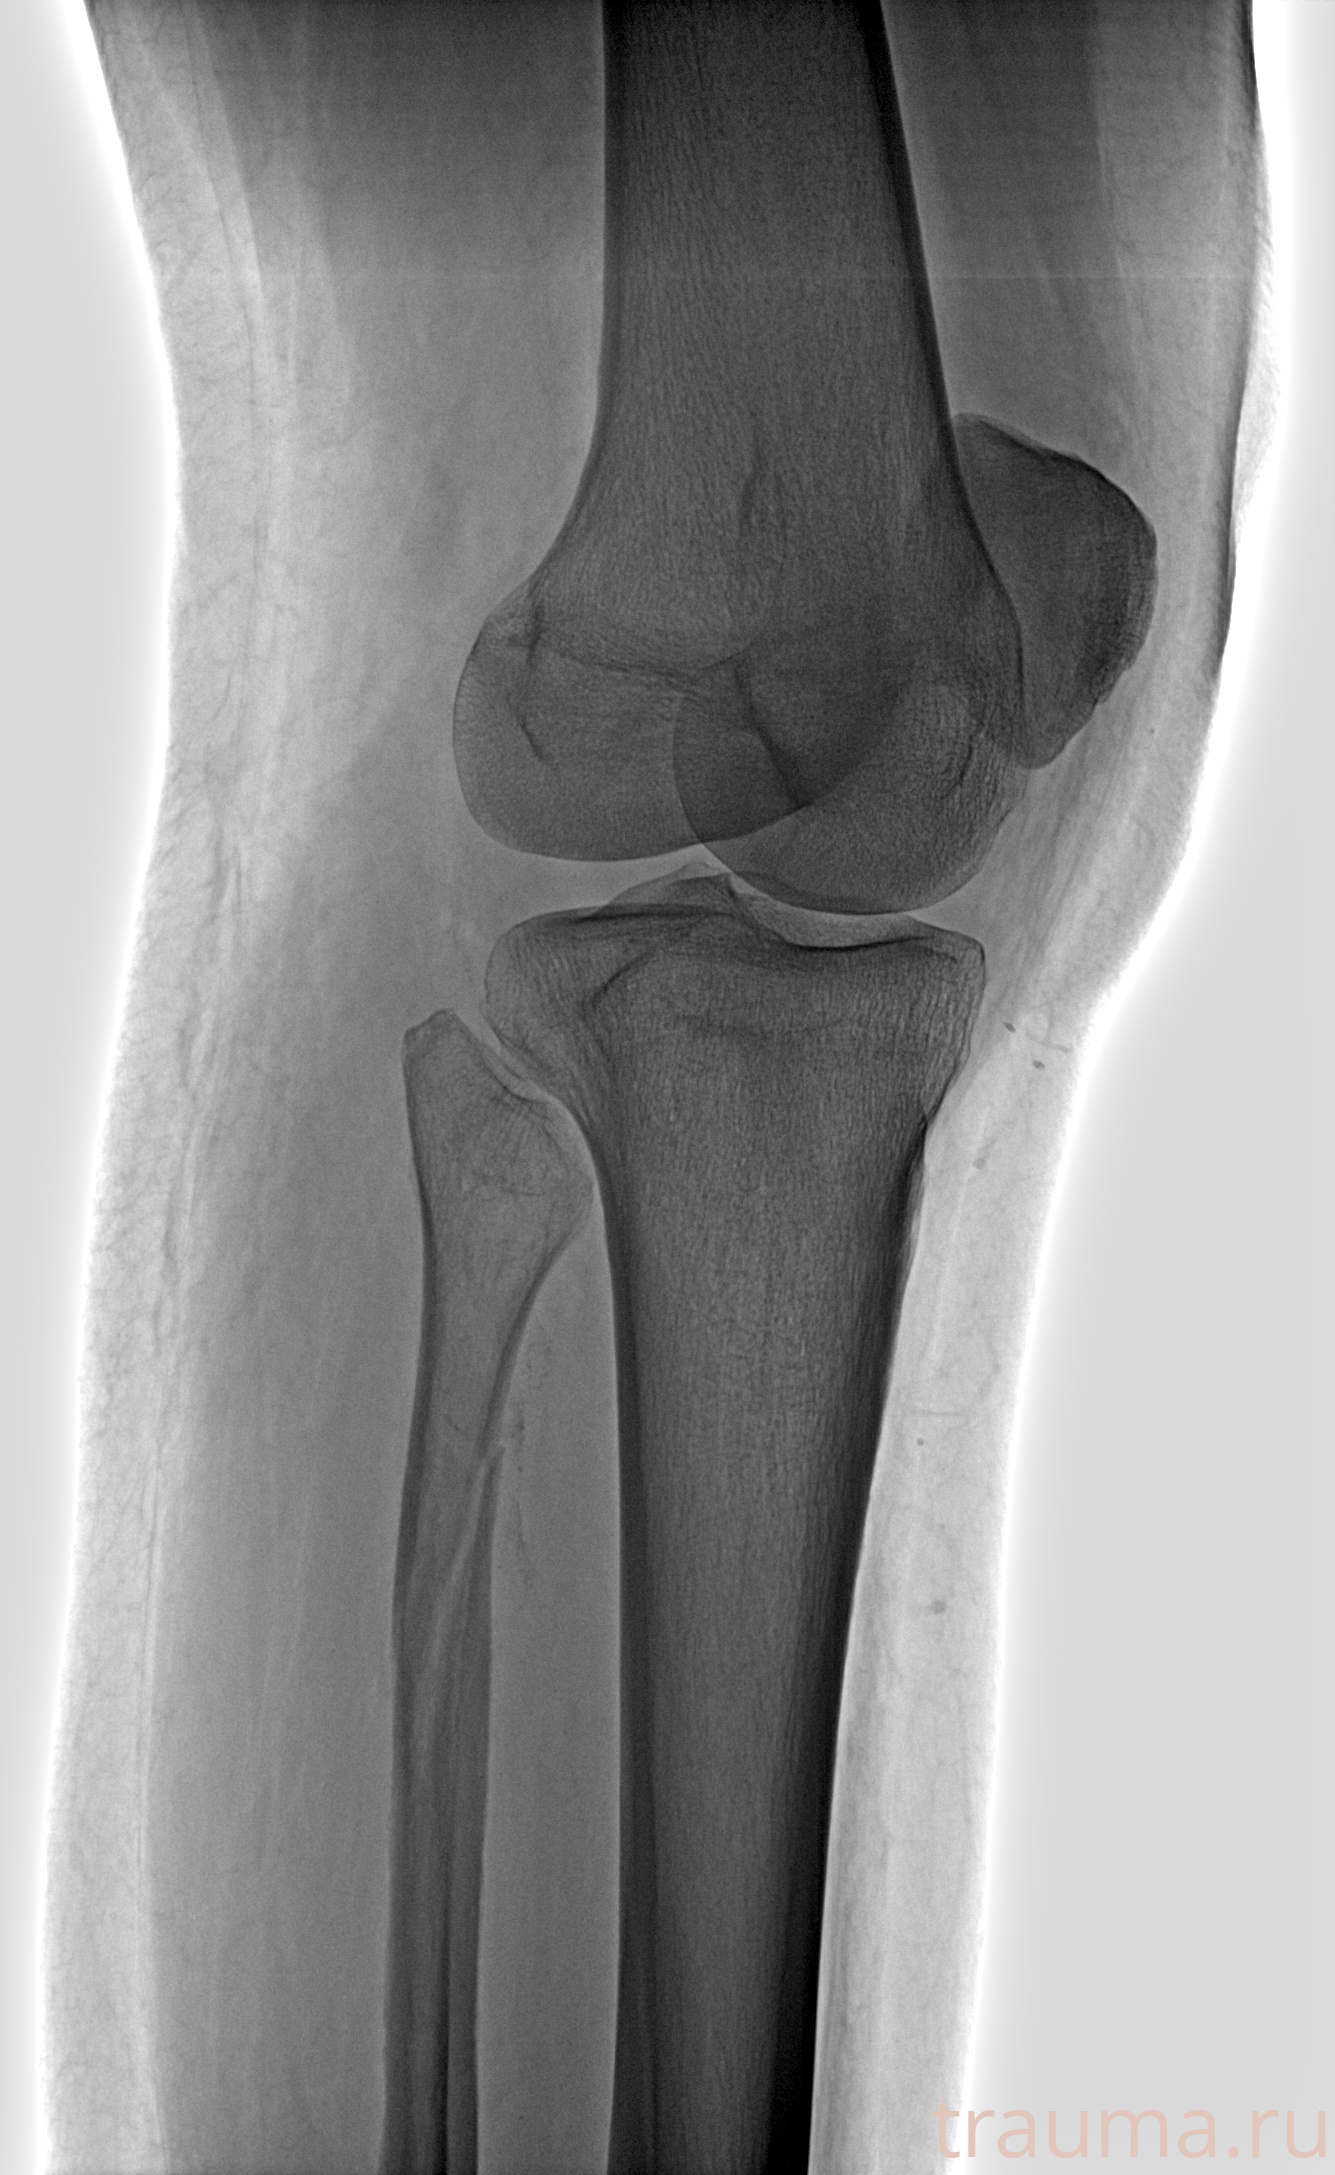

Рентгенограммы